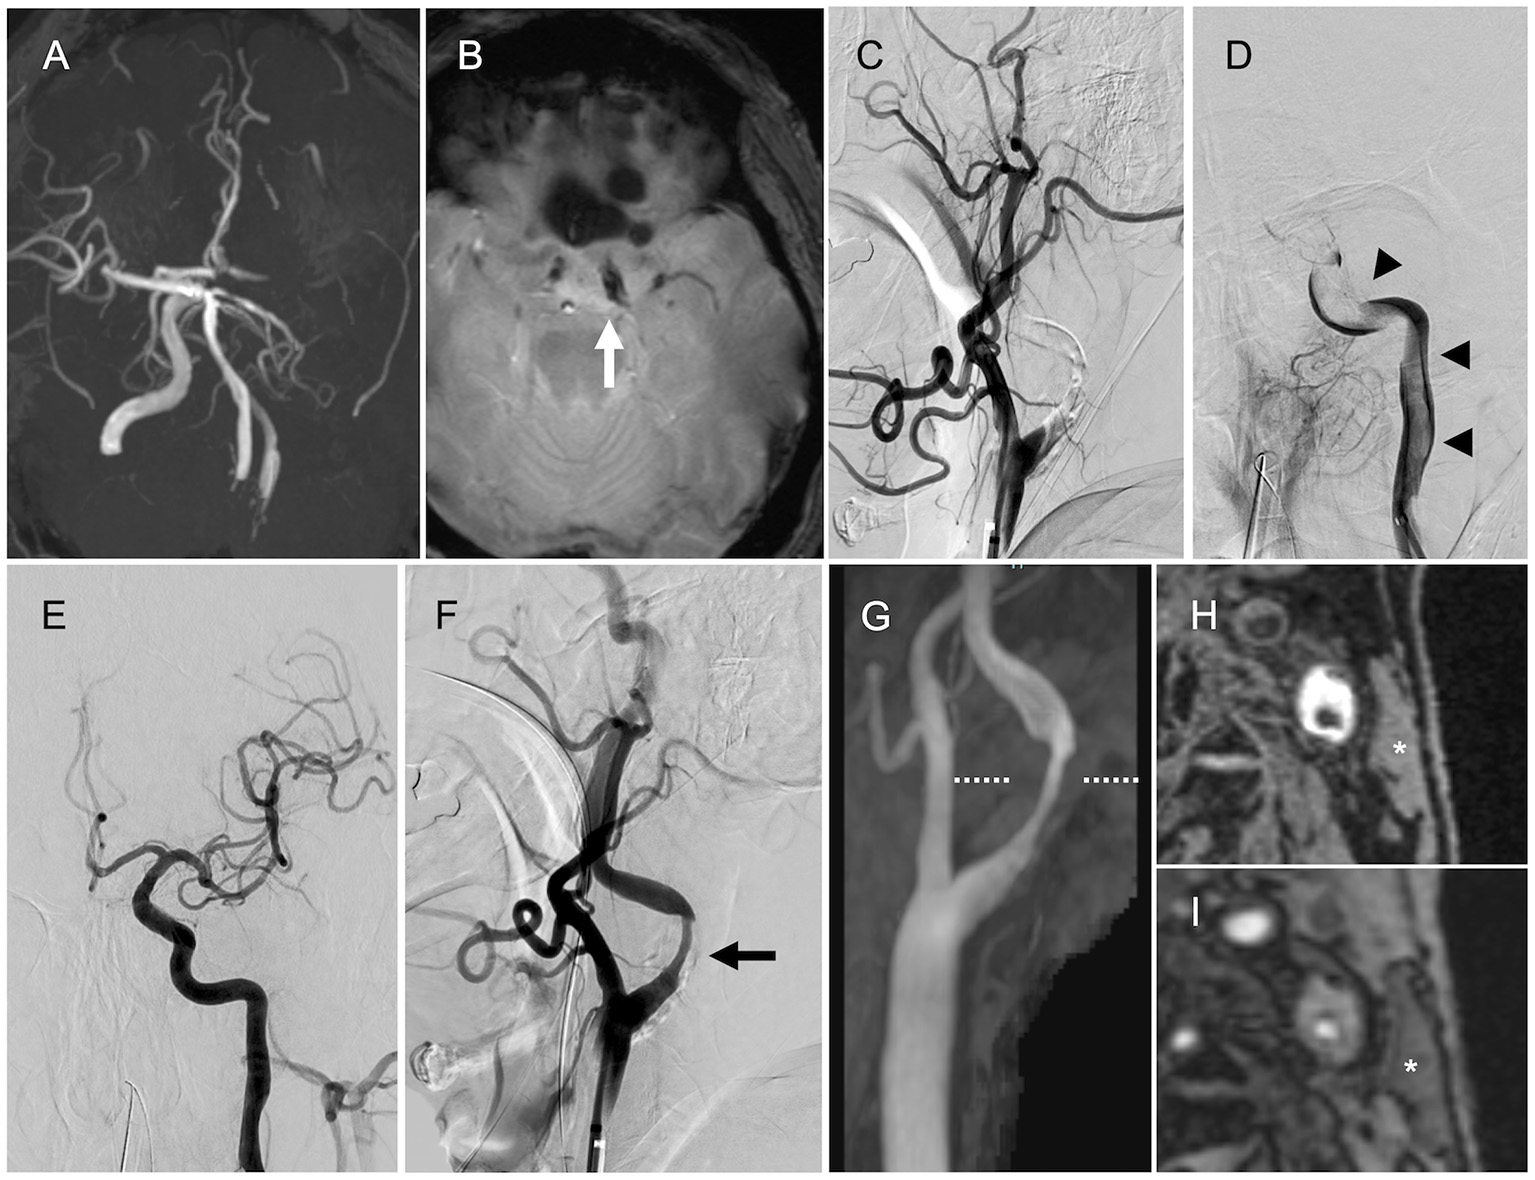

A 69-year-old man with a history of hypertension presented with global aphasia and right hemiplegia of abrupt onset. He was transferred to our institute after 13 h after the last known well-time. His baseline National Institutes of Health Stroke Scale score was 24. Diffusion-weighted magnetic resonance imaging (MRI) revealed acute infarcts in the left parietal lobe. MR angiography revealed the left ICA occlusion (Figure 1A). T2*-weighted MRI performed as the routine protocol showed a susceptibility vessel sign at the top of the ICA (Figure 1B). Hence, MT was performed after obtaining informed consent for the procedure from the patient's family. Patient's consent was obtained for publication of this report.

Magnetic resonance imaging (MRI) and angiography findings. (A) Magnetic resonance angiography (MRA) showing the left internal carotid artery (ICA) occlusion. (B) T2*-weighted MRI showing the susceptibility vessel sign at the top of the ICA (arrow). (C) Left internal carotid angiography showing the left proximal ICA occlusion (lateral view). (D) Angiography via the aspiration catheter in the cervical ICA showing a continuous filling defect (arrowheads) from the cervical ICA to the intracranial ICA (anteroposterior view). (E) Final angiography showing successful reperfusion (anteroposterior view). (F) Final angiography showing the left ICA stenosis (arrow, lateral view). (G) Neck MRA showing the left ICA stenosis. (H,I) Magnetization-prepared rapid gradient-echo image and maximum intensity projection images from time-of-flight MRA (level of the dotted line) showing high signal intensity in the plaque compared with the sternocleidomastoid muscle (asterisk).

The initial left common carotid angiography showed occlusion of the proximal ICA (Figure 1C). The aspiration catheter was navigated to the cervical ICA through the site of occluded segment of the proximal ICA. Angiography via the aspiration catheter revealed a large filling defect that extended from the cervical ICA to the intracranial ICA (Figure 1D). We deployed the stent retriever from the M1 segment of the middle cerebral artery (MCA) into the cavernous portion of the ICA. After the microcatheter was removed, the aspiration catheter was advanced to the intracranial ICA until the drip rate slowed. Then, we pulled the stent retriever and aspiration catheter as a unit into the balloon-guiding catheter. Successful reperfusion was achieved with a total of five passes by the above technique (four passes with Solitaire Platinum® 6 × 40 mm, Medtronic, Irvine, California, USA, and Penumbra ACE 60 aspiration catheter, Penumbra Inc., Alameda, CA, USA; one pass with Trevo® 4 × 20 mm, Stryker Neurovascular, Fremont, California, USA, and Penumbra ACE 60 aspiration catheter). Large red thrombi were retrieved with each pass. The final angiogram showed modified Thrombolysis in Cerebral Ischemia grade 2b reperfusion and stenosis in the proximal ICA (Figure 1E). The stenosis rate was 65% according to North American Symptomatic Carotid Endarterectomy Trial criteria (Figure 1F).

After the MT, we performed transthoracic and transesophageal echocardiography, along with electrocardiographic monitoring as the diagnostic workup of the embolic source, to determine if there was any other potential embolic source apart from the stenotic left ICA. However, no cardiac embolic sources were detected. Carotid artery ultrasonography showed severe stenosis with an echolucent plaque in the proximal ICA. Peak systolic flow velocity was 1.9 m/s. We have added neck MRI to evaluate the characteristics of the carotid plaque. Neck magnetization-prepared rapid gradient-echo image and maximum intensity projection images from time-of-flight MR angiography showed high signal intensity in the plaque compared with the sternocleidomastoid muscle (Figures 1G–I), indicating a vulnerable plaque. Although there were no embolic sources other than the carotid plaque, the possibility of cardiac source of embolism including covert atrial fibrillation could be completely excluded because of the large volume of retrieved thrombi atypical of LAA.